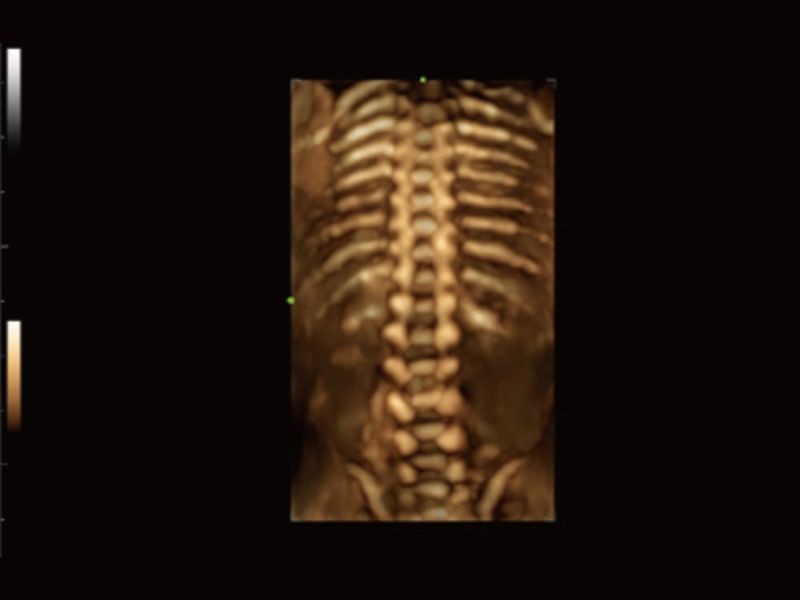

Cena Inteligente 3D

Solução obstétrica inteligente full-stack com tecnologia ZST⁺